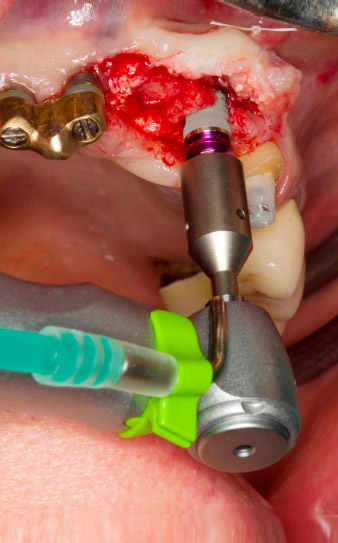

la perforazione pilota è eseguita con il nuovo dispositivo Implatmed e il manipolo contrangolo Ws-56L

Fig. 2: Due mesi dopo si è eseguita perforazione pilota con il nuovo motore Implantmed e il manipolo contrangolo WS-56L (programma P1, velocità 1:1). Il raffreddamento avviene con il tubo spray posizionato sulla sinistra (per utenti destrorsi).